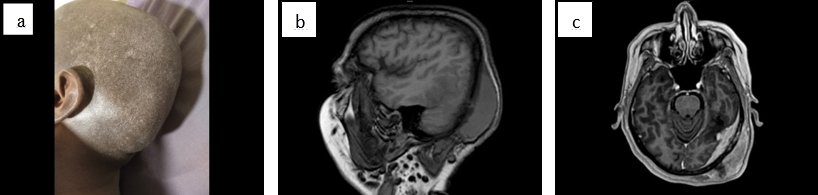

A 40 years old female was presented with a diffuse swelling in the left side of the scalp since 3 months of duration and progressively enlarging in size. On local Examination of the scalp, there was a diffuse swelling in the left parietal and occipital region of scalp. Magnetic resonance Imaging (MRI) showed contrast enhancing mass of size 8.3*3.5*5.2 cm arising from left parieto occipital bone with adjacent dura. The lesion is involving both marrow as well as cortex with infiltration of the adjacent dura with significant subgaleal component reported as differential diagnosis of 1) En plaque meningioma; 2 Solitary fibrous tumor of the dura; 3 Metastasis ([Figure 1] a,b,c).